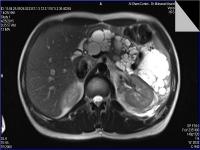

Medical imaging is an important investigative tool will help doctors to reach for the diagnosis of certain diseases, and the the advanced and high-quality imaging technologies are an important factor in maintaining the health of patients and accurate diagnosis of pathological lesions.